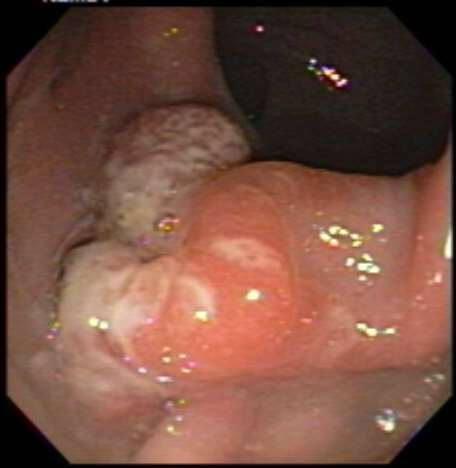

Outcome of the case. In our patient, further questioning revealed that he had been observed to spend a lot of time on the toilet. He admitted to self-digitation and straining. He was hesitant to admit these symptoms. He was counseled and was put on high-fiber diet and a daily bedtime dose of mineral oil. At follow-up 1 year later, he reported marked improvement. He noted that he usually has 1 soft bowel movement daily, and that he occasionally notices blood in small amounts. He claims to no longer need to strain and to have stopped self-digitation. Colonoscopy showed marked improvement, with only one polypoidal lesion noted in the anterior rectum (Figure 3).

Figure 3. A recent colonoscopy image showing only 1 lesion, and the others healed.